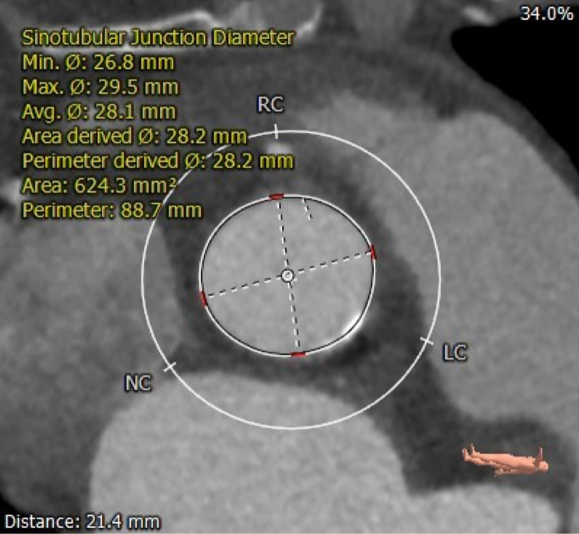

主动脉根部评估

CT 数据显示该患者为三叶式主动脉瓣